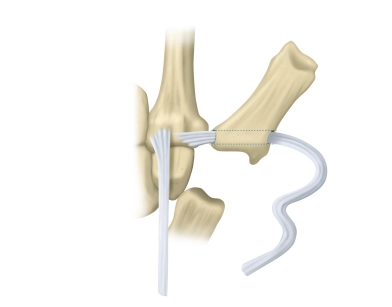

Intervenciones en huesos y articulaciones

Artroplastia de resección-suspensión según Epping para rizartrosis